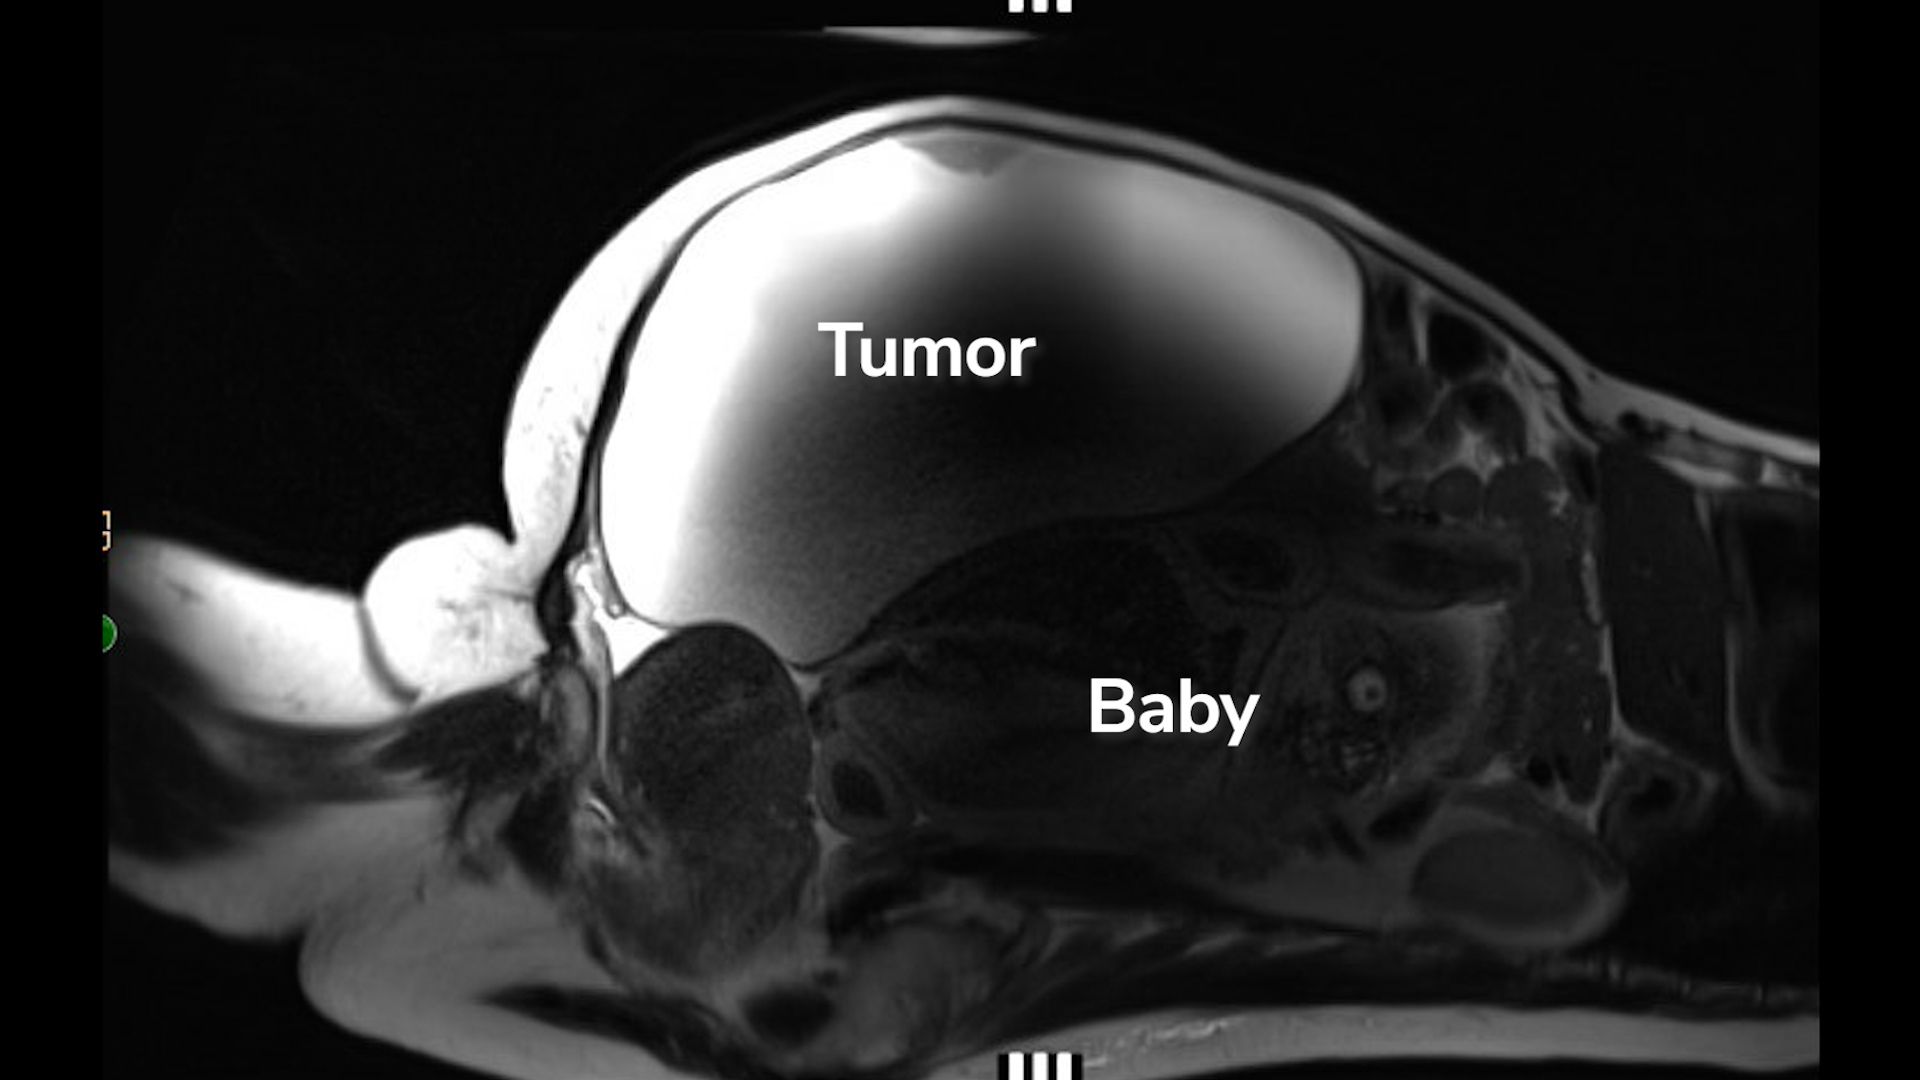

Nhân vật chính là Suze Lopez, 41 tuổi, y tá khoa cấp cứu tại thành phố Bakersfield. Trước khi bước vào ca phẫu thuật theo lịch hẹn, Lopez được thực hiện xét nghiệm thai kỳ định kỳ và bất ngờ cho kết quả dương tính. Các bác sĩ sau đó phát hiện cô không chỉ mang thai, mà còn đang mang một em bé đủ tháng phát triển bên ngoài tử cung, bị che khuất hoàn toàn phía sau một khối u nang buồng trứng nặng gần 10 kg.

Bác sĩ qua siêu âm phát hiện thai nhi nằm ngay phía dưới khối u nang buồng trứng khổng lồ của người phụ nữ (Nguồn ảnh: Cedars-Sinai)

Tại đây, các bác sĩ phát hiện huyết áp của Lopez tăng cao bất thường. Sau khi tiến hành xét nghiệm máu, chụp MRI và siêu âm, họ xác định đây là một trường hợp thai ngoài tử cung ở ổ bụng cực kỳ hiếm. Thai nhi nằm gần gan, phần lưng tựa lên tử cung.

“Chính em bé phát triển phía sau khối u đã đẩy các cơ quan khác ra ngoài, khiến bệnh nhân không hề biết mình đang mang thai,” bác sĩ John Ozimek, Giám đốc y khoa khoa Sản và Chăm sóc Thai kỳ nguy cơ cao tại Cedars-Sinai, cho biết. Ông nhấn mạnh: “Một thai kỳ sống sót và phát triển xa khỏi tử cung đến mức này gần như chưa từng có tiền lệ.”